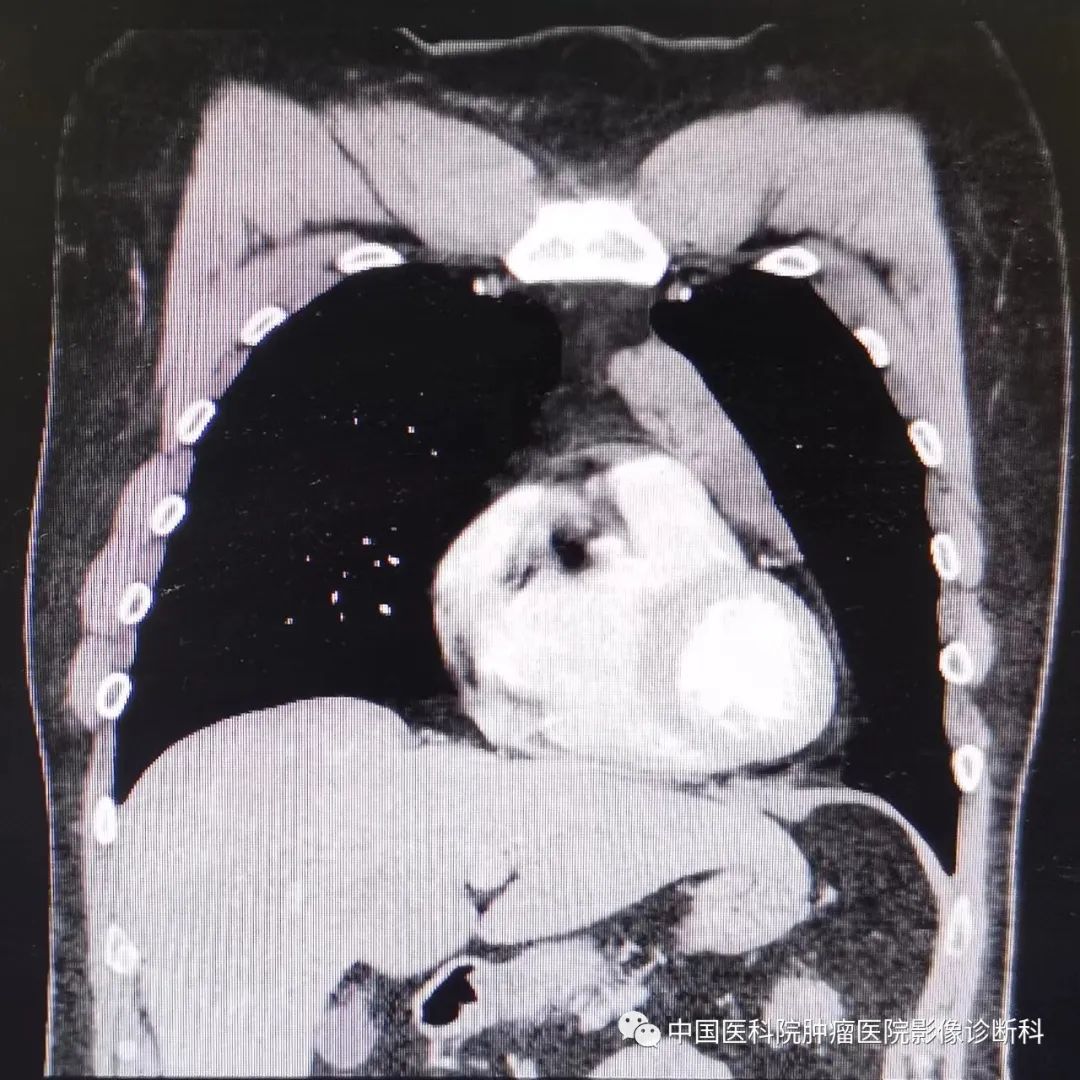

增强CT冠状位纵隔窗

1.在CT图像上,关于病灶的描述,正确的是:(ABC)

A: 前纵隔不规则肿块

B:肿块主要呈软组织密度,少部分液体密度

C:增强呈不均匀强化

D:肿块内见钙化

手术肉眼所见:前纵隔肿物,大小4.3×3.2×1.9 cm,切面灰白灰黄实性质硬界不清,呈多结节状,部分呈囊性,囊内壁光滑,壁厚0.1cm,紧邻纵隔胸膜。

病理诊断意见:肿瘤组织,呈实性片状,可见核分裂象,伴肉芽肿形成,结合形态及免疫组化结果,符合精原细胞瘤,伴囊性变及少许灶状钙化,局灶紧邻被膜及纵隔胸膜。

免疫组化结果:AE1/AE3(-),甲胎蛋白(AFP)(-),CD117(2+),CD30(-),人绒毛膜促性腺激素(HCG)(-),0ct3/4(1+),PLAP(3+),SALL4(3+),波形蛋白(Vimentin)(-)